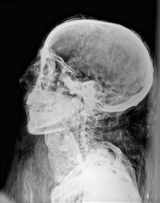

2. ミイラ(頭部画像(1)) Mummy image (head 1)

鮮明なデジタル画像は,頭頂葉に今まで分からなかった腐食を捉えた。このことは,このミイラが生前,寄生虫に蝕まれていたか,貧血,あるいは栄養失調の状態であったことを示している。

撮影および画像提供: フィールド博物館 |